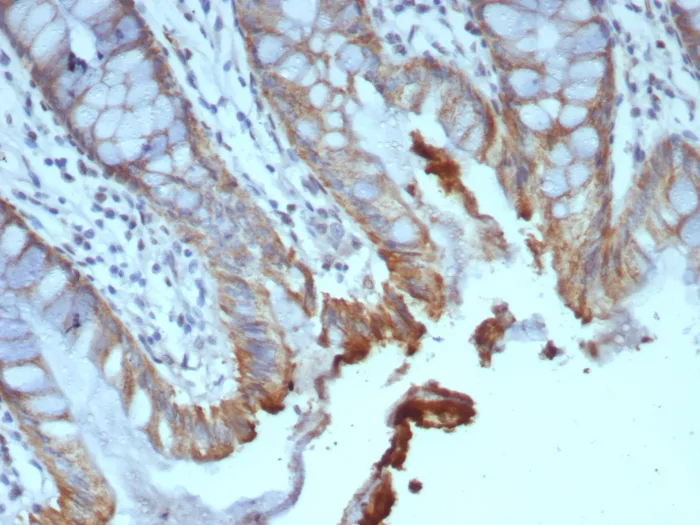

Formalin-fixed, paraffin-embedded human colon carcinoma stained with ICOS-L Mouse Monoclonal Antibody (ICOSL/7700). HIER: Tris/EDTA, pH9.0, 45min. 2°C: HRP-polymer, 30min. DAB, 5min.